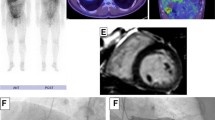

He was admitted to our coronary care unit with severe dilated cardiac myopathy and LV failure with a provisional diagnosis of post-viral myocarditis. He was treated with low-dose frusemide and an ACE inhibitor. Serology for human immunodeficiency virus (HIV), hepatitis B virus (HBV), hepatitis C virus (HCV), and varicella zoster virus (VZV) were all non-reactive. Interferon-gamma release assay (IGRA) for Mycobacterium tuberculosis (MTB) was negative. CMR demonstrated severe dilated non-ischemic cardiomyopathy with a LVEF of 17%. No focal areas of abnormal gadolinium (GAD) enhancement were found in the myocardium, which was reported as within normal limits (Fig. 1ai). It should be noted that subsequent review by a third party with expertise in CMR for the purpose of publication found the scan to be indeterminate based on technical reasons, and this is discussed further below. Dermatology and Ophthalmology review and examination found no evidence of cutaneous or ocular sarcoidosis. Additional markers for sarcoidosis were unrewarding including: ACE, 16 U/L (RR 8 to 64 U/L); 1,25 dihydroxyvitamin D, 54 pmol/L (RR 60 to 100); and urine calcium, 1.9 mmol/L. Autoimmune serology including antinuclear antibodies (ANA), extractable nuclear antigens (anti-ENA), antineutrophil cytoplasmic antibodies (ANCA), cyclic citrullinated peptide (anti-CCP), double-stranded DNA (dsDNA), C3, C4, and rheumatoid factor were all within normal limits.

Cardiac magnetic resonance imaging with gadolinium and 18F-fluorodeoxyglucose-positron emission tomography at time of diagnosis and during follow-up. Advanced imaging for a Patient 1 shows i cardiac magnetic resonance imaging reported in the clinical setting as within normal limits. Re-review for the purposes of publication found the scan was of insufficient quality to accurately detect presence of delayed enhancement. ii 18F-fluorodeoxyglucose-positron emission tomography at time of presentation demonstrates abnormal heterogeneous and moderate-to-markedly increased metabolism in hilar and mediastinal nodes consistent with cardiac sarcoidosis, as well as cardiomegaly and diffuse uptake in both ventricles and the right atrium. iii Progress 18F-fluorodeoxyglucose-positron emission tomography following 3 months’ treatment with prednisone and methotrexate demonstrates response to treatment with a reduction in the size and metabolism of the hilar and mediastinal lymph nodes. In addition, the heart is smaller and the increased uptake seen in the right ventricle and the right atrium on the initial scan has resolved, although there is persistent metabolism in the septum. iv Progress 18F-fluorodeoxyglucose-positron emission tomography following 17 months of immunosuppression demonstrates response to treatment with complete resolution of abnormal metabolism in the myocardium, but persisting areas of avidity in the mediastinal and hilar lymph nodes. b Patient 2 shows i cardiac magnetic resonance imaging with no abnormalities detected at presentation. ii 18F-fluorodeoxyglucose-positron emission tomography at time of presentation demonstrates abnormal active sites of focal myocardial inflammation in the basal anteroseptum, basal septum, and inferior walls that was consistent with cardiac sarcoidosis. iii Progress 18F-fluorodeoxyglucose-positron emission tomography following 6 months of immunosuppression with prednisone and methotrexate demonstrates resolution of previously abnormal focal increased 18F-fluorodeoxyglucose accumulation in the left ventricle consistent with resolution of areas of inflammation

He proceeded to FDG-PET following a 6-hour fast, to investigate for underlying CS. This showed heterogeneous and moderate-to-marked increased metabolism in hilar and mediastinal nodes consistent with sarcoidosis, as well as cardiomegaly and diffuse uptake in both ventricles and his right atrium. Although not classic for CS, where uptake is usually patchy, CS could not be excluded (Fig. 1aii). Endomyocardial biopsy was discussed and considered too great a risk in the setting of low LVEF and recent thrombolysis. He was commenced on systemic immunosuppression with prednisone 1 mg/kg orally administered daily and methotrexate. He was discharged on the above immunosuppression together with warfarin, bisoprolol, frusemide, ivabradine, magnesium aspartate, ramipril, and spironolactone. The decision for automated implantable cardiac defibrillator (AICD) was deferred and out-patient cardiac rehabilitation and transplant referral arranged.

A review at 2 weeks demonstrated a remarkable recovery with increased LVEF to 29% (from 10 to 15%). Our patient self-reported energy levels higher than at any time in the preceding 2 years, prompting a return to full-time work. Three months after the initial presentation he presented with worsening CCF and was found to be in atrial fibrillation (AF). He underwent successful direct current (DC) cardioversion and was commenced on sotalol. A progress FDG-PET at that time demonstrated response to treatment with a reduction in the size and metabolism of the hilar and mediastinal lymph nodes. In addition, his heart was smaller and the increased uptake seen in the right ventricle and the right atrium on the initial scan had resolved, although there was still persistent metabolism in the septum (Fig. 1aiii). The LVEF progressively improved from 47% at 4 months to 53% at 10 months. A progress FDG-PET at 17 months found no regions of increased metabolism in the myocardium, but persisting areas of avidity in his mediastinal and hilar lymph nodes (Fig. 1aiv). He remains clinically well and asymptomatic from systemic sarcoidosis or CS. Cardiac transplantation is no longer a consideration.

Biochemical investigations including serum ACE of 24 (8 to 64), 1,25 vitamin D of 99 (60 to 100), and urine calcium of 6.6 nmol/L were all within normal limits. Dermatology and Ophthalmology review found no evidence of cutaneous or ocular sarcoidosis. A second CMR found normal biventricular size and systolic function and no late GAD enhancement seen in LV to suggest sarcoid involvement (Fig. 1bi). For the purposes of publication, the second CMR was subsequently reviewed by the same third party with specific expertise as used in Case 1. There was agreement that this CMR was within normal limits.

She proceeded to cardiac FDG-PET due to high clinical suspicion of CS despite two CMR scans within normal limits. Her BSL prior to scanning was 6.6 mmol/L following a 12-hour fast. The FDG-PET scan was suggestive of CS with active sites of focal myocardial inflammation in the basal anteroseptum, basal septum, and inferior walls (Fig. 1bii). She underwent successful permanent pacemaker (PPM)-AICD insertion due to risk of future VT and sudden cardiac death, and was commenced on metoprolol. She was commenced on prednisone 1 mg/kg orally administered daily and methotrexate. She was discharged and has had no further cardiac events. A repeat cardiac FDG-PET at 6 months demonstrated resolution of previously abnormal focal increased FDG accumulation in the LV consistent with resolution of areas of inflammation (see Fig. 1biii). The salient features of the two presented cases are shown in Table 3.

Ohira et al. studied the diagnosis of CS in 21 patients who underwent both FDG-PET and CMR using the JMHW 2007 criteria as the gold standard [29, 35]. They found FDG-PET had a higher sensitivity for the diagnosis of CS (88% versus 75%) but lower specificity (39% versus 77%; [35]). More recent studies looking specifically at conduction delay have found patients with acute AV node block (such as Case 2) were more likely to have abnormal FDG-PET and normal CMR compared with patients with chronic mild CS presenting with other conduction abnormalities (33% compared with 0%) [36, 37]. It should be noted that image acquisition and interpretation of both CMR and FDG-PET for the diagnosis of CS can be challenging and requires specific expertise [10]. In terms of CMR, expertise is required in MRI set-up, quality control, scan supervision, and image interpretation. In fact, a re-review of CMR in the above cases found that the scan in Case 1 was indeterminate rather than a true negative due inadequate nulling of the myocardium in the delayed enhancement series. The resolution of FDG-PET avidity on serial imaging seen with the cases above is reassuring, especially given recent data demonstrating improved PET parameters correlate with improved LVEF and other clinical outcome measures [38, 39].